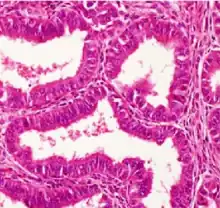

| Mucinous tumor | 15% | 8.8% | Benign mucinous tumors of the ovary consist of simple, nonstratified columnar epithelium with basally-located hyperchromatic nuclei and resemble gastric foveolar epithelium.[6] |  | |